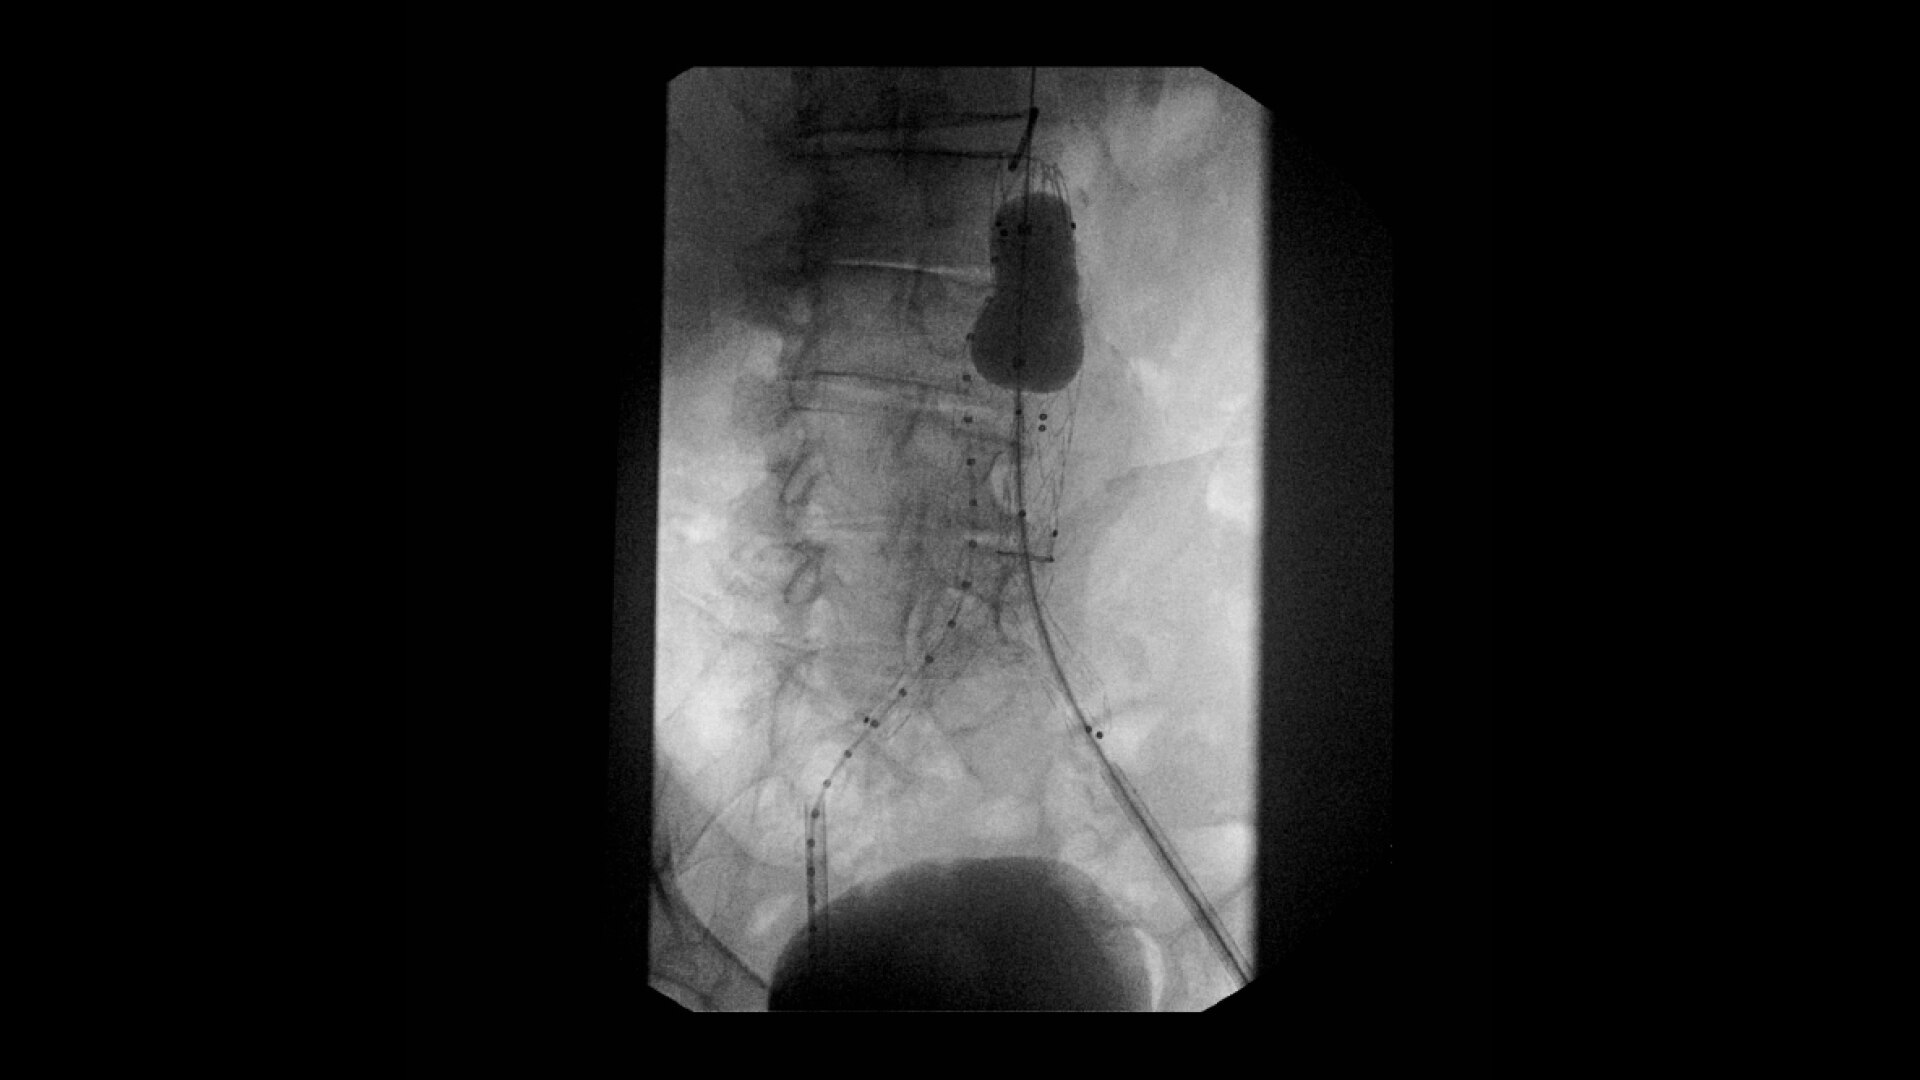

OEC C-arms are used by interventionalists and surgeons to obtain vascular imaging during peripheral to contrast run-off procedures. Superb resolution, even in the presence of motion, enables easy identification of anatomical landmarks and the extremity of the catheter, even as catheter tip moves.

Complex vascular procedures require powerful imaging systems. OEC premium C-arms perform in a variety of procedures such as:

•Abdominal aortic aneurysm (AAA) stent and balloon deployment

• Atherectomy

• Dialysis declot

• Infrarenal aortic aneurysm repair

• Recanalization and stent placement in iliac arteries

• Recanalization of the superior mesenteric artery

• Stent implant in peripheral artery

• Vascular long lesion treatment